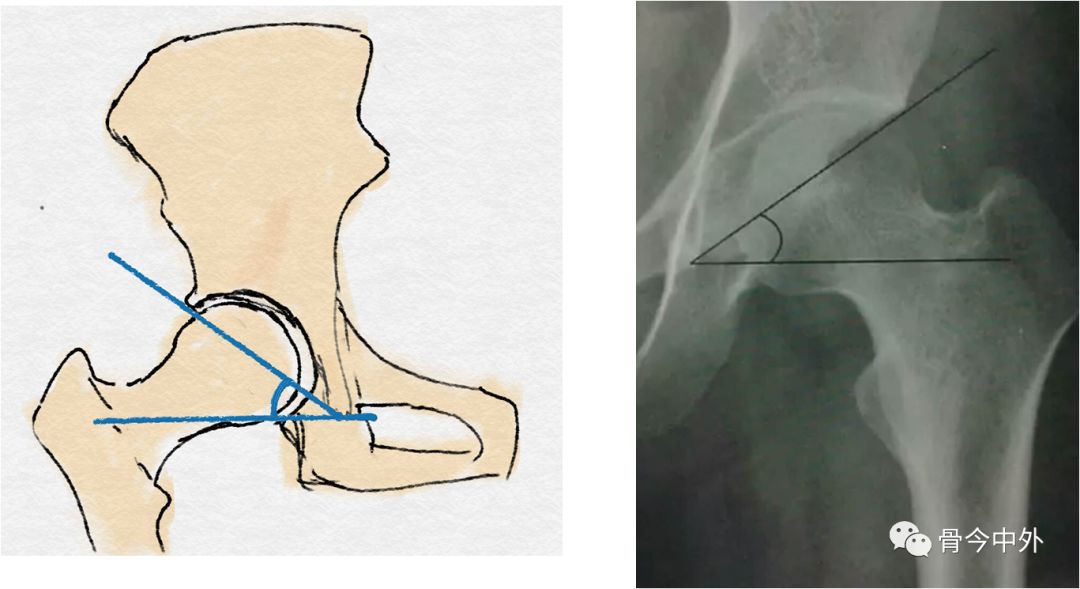

sharp角

sharp角:骨盆正位片上,双侧泪滴下缘连线与泪滴下缘和髋臼上缘的连线

特殊划线及测量的名称:sharp 角3.

图1a和b描述了髋臼的形态:sharp角描述了两泪滴间线连和将泪滴下端